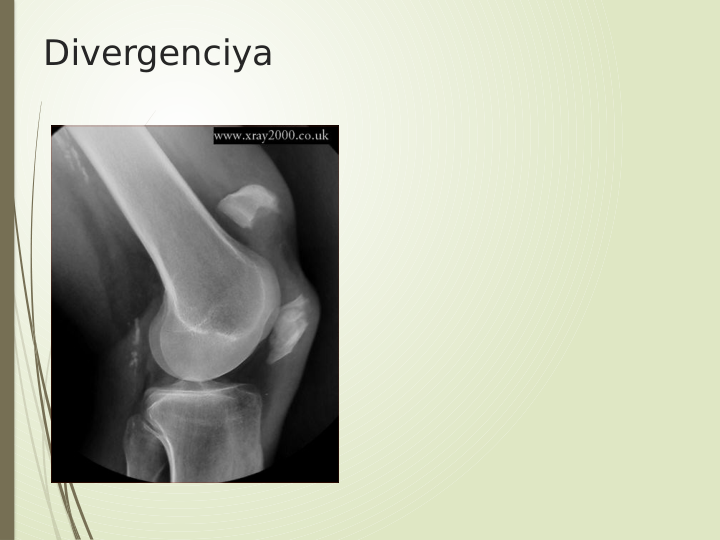

Divergenciya

Logotip